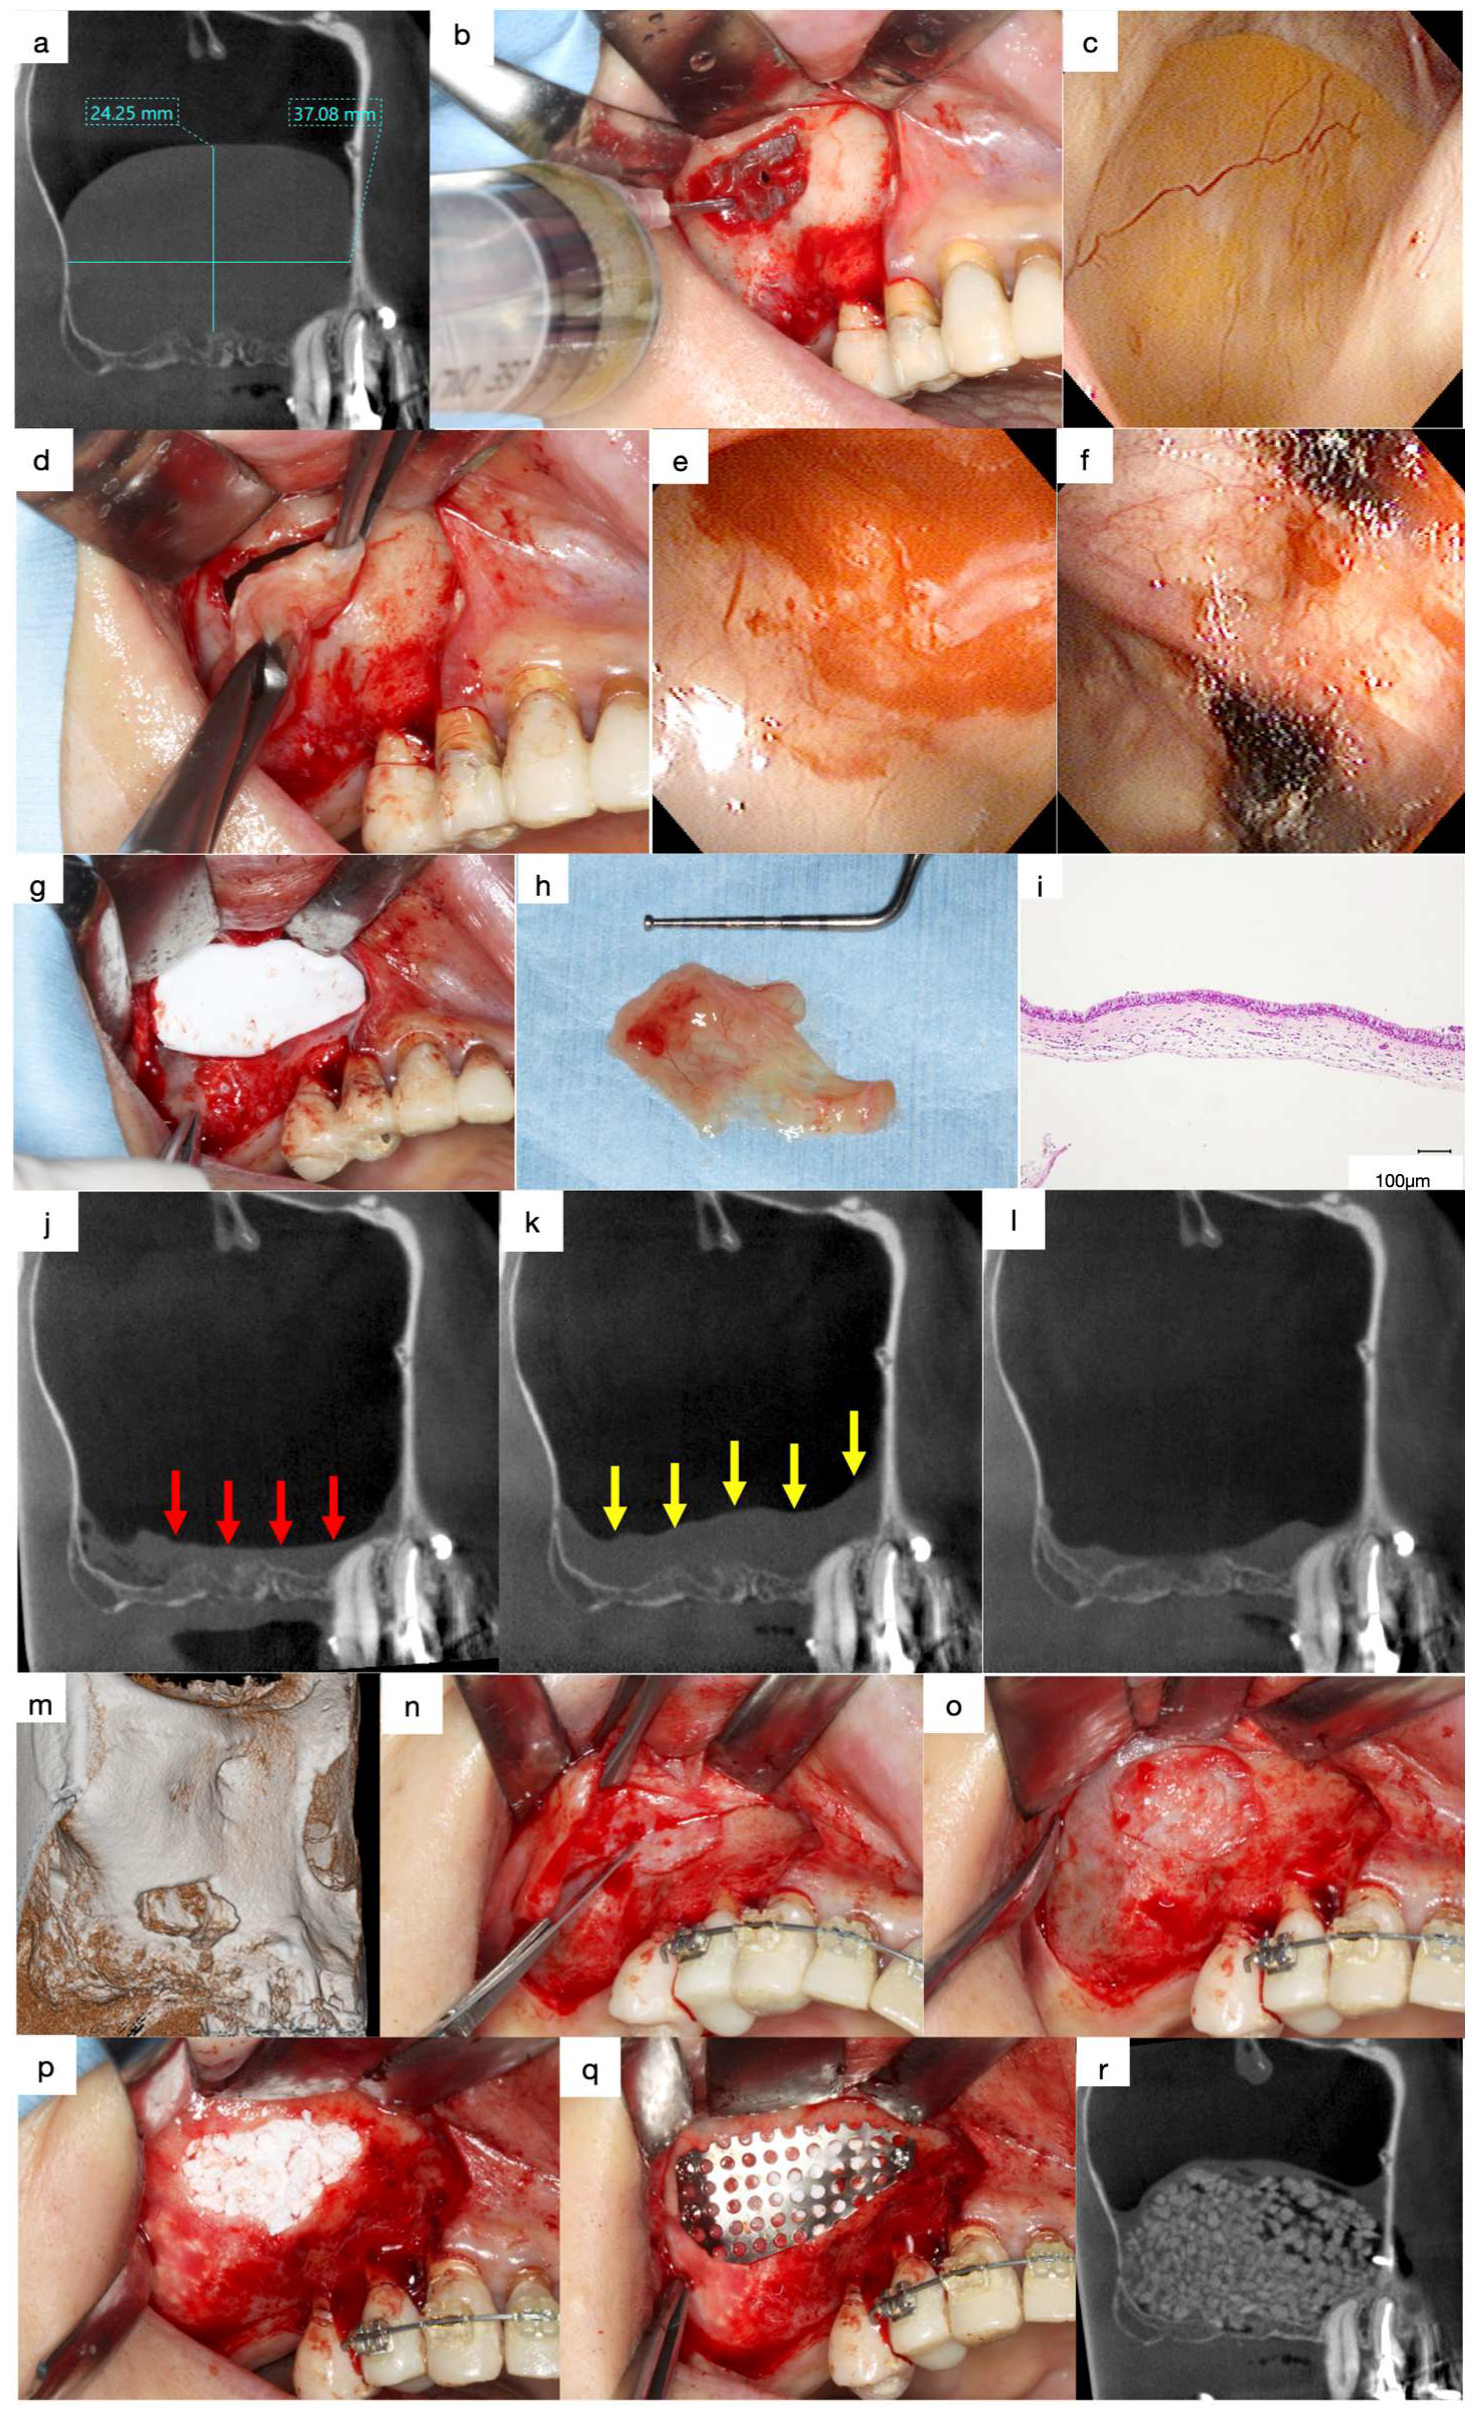

Figure 5.

(a) Mesiodistal section of the CT images acquired at the first visit. A large, well-defined, and faint radiopaque lesion can be observed in the maxillary sinus. (b) Preliminary suction of the lesion contents was performed using a fine 18-gauge needle. (c) Endoscopic view of the antral pseudocyst (AP) after suction of the contents. The AP has reduced in size compared to that observed on the CT images during the preliminary section. (d) The surface of the AP was clamped with forceps and herniated through the bony window with gentle outwards traction. (e) Endoscopic view of the enucleated area. A contentious haemorrhage was observed at the base of the AP. (f) Oxidised regenerated cellulose was applied to stop bleeding. (g) The bony window is covered with a resorbable collagen membrane to reduce blood flow into the sinus cavity. (h) The AP was enucleated as a lump with a base. (i) Histological specimen of the enucleated AP (haematoxylin and eosin staining). The outer surface of the lesion was lined with ciliated columnar epithelium and the inner surface was lined with fibrous connective tissue without epithelium. (j) Mesiodistal section of the CT image obtained after enucleation. A flat, faintly radiopaque area can be observed, demonstrating an accumulation of physiological saline or blood at the bottom of the maxillary sinus (red arrows). (k) Swelling of the sinus membrane increased one-week following enucleation (yellow arrows). (l) Swelling of the sinus membrane decreased three months after enucleation. (m) Volume-rendering image obtained three months after enucleation. The bone defect persists in the bony window. (n) Dissection of the scar tissue between the sinus membrane and oral mucosa was necessary at the bone defect area to avoid perforation of the sinus cavity. (o) Scar tissue was observed in the bone defect area without perforation after the elevation of the mucoperiosteal flap. (p) β-TCP granules fill the space between the elevated periosteum and the exposed bone surface of the maxillary sinus. (q) The bony window was tightly covered with a titanium mesh plate and three titanium microscrews. (r) Mesiodistal section of the CT image obtained after sinus floor elevation. Sufficient radiopaque granules can be observed in the augmented area.

4.4. Lateral Approach after Enucleation

Swelling of the sinus membrane is observed due to traumatic stimulation one week post-surgery (Figure 5j,k), which diminishes three months later (Figure 5l). The ciliated columnar epithelium cells at the base of the AP are removed during the enucleation, and the periosteum underneath the AP is exposed. Hence, the decrease in the swelling of the sinus membrane indicates the regeneration of the columnar epithelial cells and restoration of the ciliary motility. Thus, sinus floor elevation can be performed four months following enucleation of APs.

Bone defects in the bony window persist for four months following the enucleation of APs (Figure 5m). Therefore, dissection of the scar tissues between the sinus membrane and oral mucosa must be performed in the area with the bone defect during the elevation of the mucoperiosteal flap for sinus floor elevation using the lateral approach (Figure 5n,o). The periosteum underneath the sinus membrane is elevated after enlarging the bony window, and the β-TCP granules are filled in the space between the elevated periosteum and the exposed bone surface of the maxillary sinus (Figure 5p). The bony window is covered tightly with a titanium mesh plate and three titanium micro screws to avoid the migration of the β-TCP granules due to the postoperative sealing of the sinus membrane (Figure 5q,r) [5].